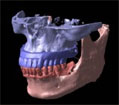

下記の写真をご覧下さい。

これは、吉本歯科医院で実際にインプラント治療(オールオンフォー)が終了した患者さまの顎の状態を3D立体構築画像で見た状態です。

吉本歯科医院でインプラント治療を行う患者さまの顎の状態は、CT画像だけでなくここまで立体化されたものが手術前には手元にあり、シミュレーションを行ってから実際の手術に入るような流れをとっております。

さて、この写真、黄色くうにょうにょとしているのが神経です。

本来骨の厚みがある患者さまの場合は神経の黄色い部分は骨の中に隠れているため3D立体画像で真上から見た場合かくれて見えません。

この方の場合、骨が神経の出口(オトガイ孔)まで磨り減ったためにこのように写ります。

この神経は、ちょっと難しいんですが、下歯槽管(かしそうかん)といい神経、血管が入っているトンネルのような管です。

オトガイ孔はその出口です。

左右片側の下唇および、オトガイ孔の皮膚の知覚を司る神経です。

もし手術であやまってこの神経を損傷すると、下唇およびオトガイ部が麻酔がかかったようにしびれてしまいます。

インプラント手術をしたあと、「顔がしびれだした」といった症状はこの重要な神経に傷をつけてしまったことによって起こります。

この中で、インプラントにおいて執刀する歯科医師が最も留意しなくてはならないのが下歯槽管神経との距離なのです。

インプラント体で下顎骨の中を走る神経やオトガイ孔から出た神経を傷つける可能性があるため手術の前には必ずCT撮影をし、適正な長さのインプラント体の選択が必要となります。